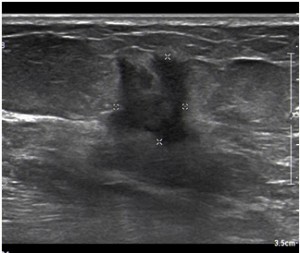

La técnica complementaria de elección es la ecografía2, que nos permite distinguir la naturaleza del nódulo, es decir, si tiene comportamiento quístico o sólido, además de sus límites, formas y ecogenicidad. Cabe decir también, que gracias a la ecografía podemos dirigir a tiempo real una biopsia por aguja gruesa (BAG), tal y como se requiere en nuestro caso.